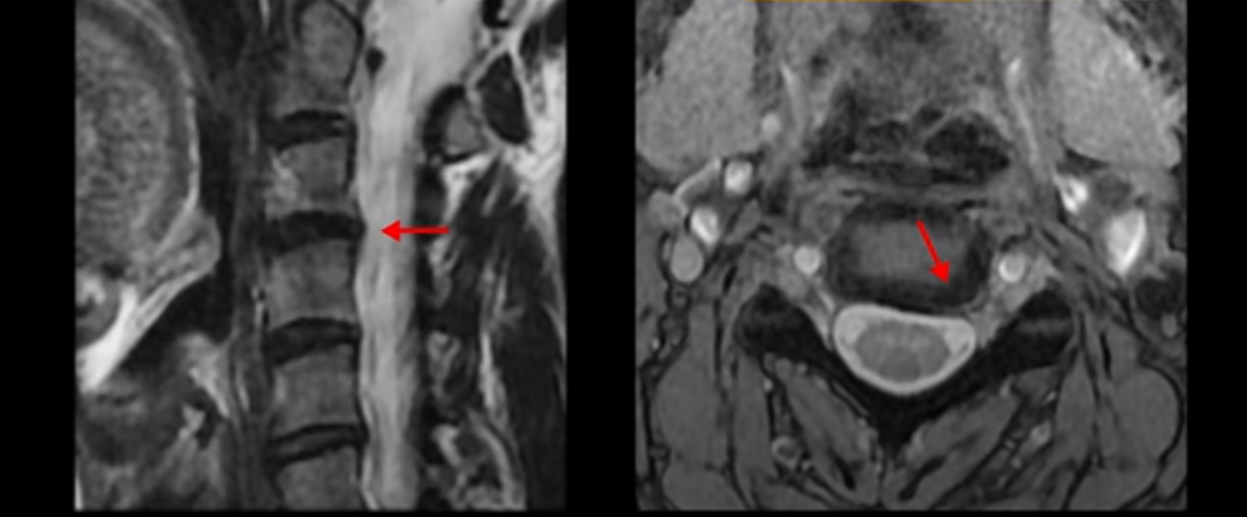

이런 목 형태를 가지면 목이 안 아플 수가 없습니다. 그리고 목에 엄청난 부담을 주기 때문에 디스크가 퇴행되면서 찢어질 가능성이 높아지죠. 이 환자분은 오른쪽과 왼쪽이 모두 저리고 아픕니다. MRI를 보면 5번 6번 디스크가 오른쪽 파열되어 아래로 흘러내려가 있습니다.

더 윗마디 3번 4번을 보면 왼쪽으로 디스크가 밀려나가 있습니다.

그래서 양쪽 어깨와 팔이 다 저리고 아픈 겁니다. 이런 신경이 눌리고 자극되는 목디스크가 왜 우리는 치료가 허리디스크보다 훨씬 더 쉽고 빠르다고 얘기하는 걸까요? 허리에 비해 입원치료 기간이 반 정도로 짧아서 평균 2주 정도 걸립니다. 참고로 이 환자분은 통원치료로 딱 8번 받은 후 이 후기를 찍으셨습니다. 목디스크가 비수술치료 성공률이 높고 빠른 이유는 목이 무게, 즉 하중을 허리에 비해 굉장히 적게 받기 때문 입니다. 그래서 여러분이 만일 수술을 고민하고 있다면, 또 신경주사가 안 듣는다면 정말로 안 해볼 이유가 없는 치료입니다.